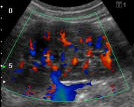

Dr. Sawant Diagnostic & Sonographic Centre - Image 1 Dr. Sawant Diagnostic & Sonographic Centre - Image 2 Dr. Sawant Diagnostic & Sonographic Centre - Image 3 Dr. Sawant Diagnostic & Sonographic Centre - Image 4